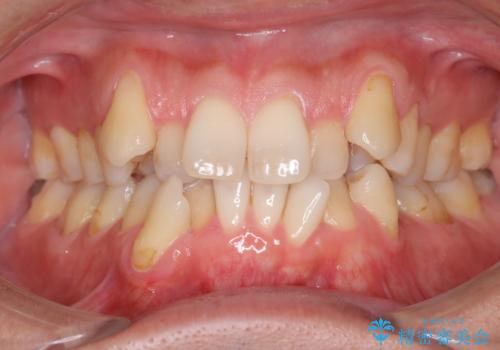

50代女性 八重歯を矯正治療 歯並びの中等度のがたつき

マウスピース矯正が煩わしい ワイヤー装置での非抜歯矯正

担当医 藤巻太一朗